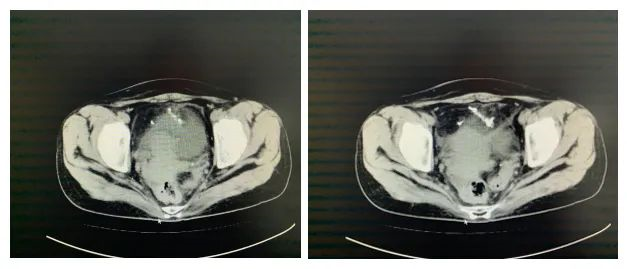

患者姜某,女,39岁,体检发现血尿10余天,追查原因,行CT检查后回报盆腔金属高密度影,部分位于膀胱腔内。

膀胱镜下可见右侧输尿管上方6cm膀胱壁可见一大小约1.0*0.5cm的异物,嵌顿于膀胱壁。精准定位后行腹腔镜手术治疗,采用超声刀充分分解粘连,沿异物边界完全游离,使用腔镜下一次性切割闭合器,离断并夹闭膀胱后壁,术程顺利。